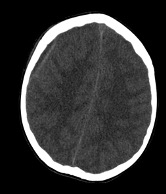

Diagnostic testing. Findings from the laboratory studies revealed an elevated white blood cell count of 33.09 c/mL, an elevated erythrocyte sedimentation rate of 122 mm/hr, and an elevated procalcitonin level of 9.61 ng/mL. Thus, the patient was started on cefepime and levetiracetam. Imaging studies demonstrated mastoiditis, a large right temporal collection of fluid concerning for early cerebritis, and ventriculitis with abscess formation and local mass effect (Figures 1-4).

Figure 1. Axial images of computed tomography scans of the head demonstrating (a, top) opacification of right mastoid sinus and right middle ear consistent with a diagnosis of otomastoiditis, (b, middle) subdural empyema in the right convexity, and (c, bottom) an ill-defined area of low attenuation in the right temporal lobe suspicious for underlying infection or mass.